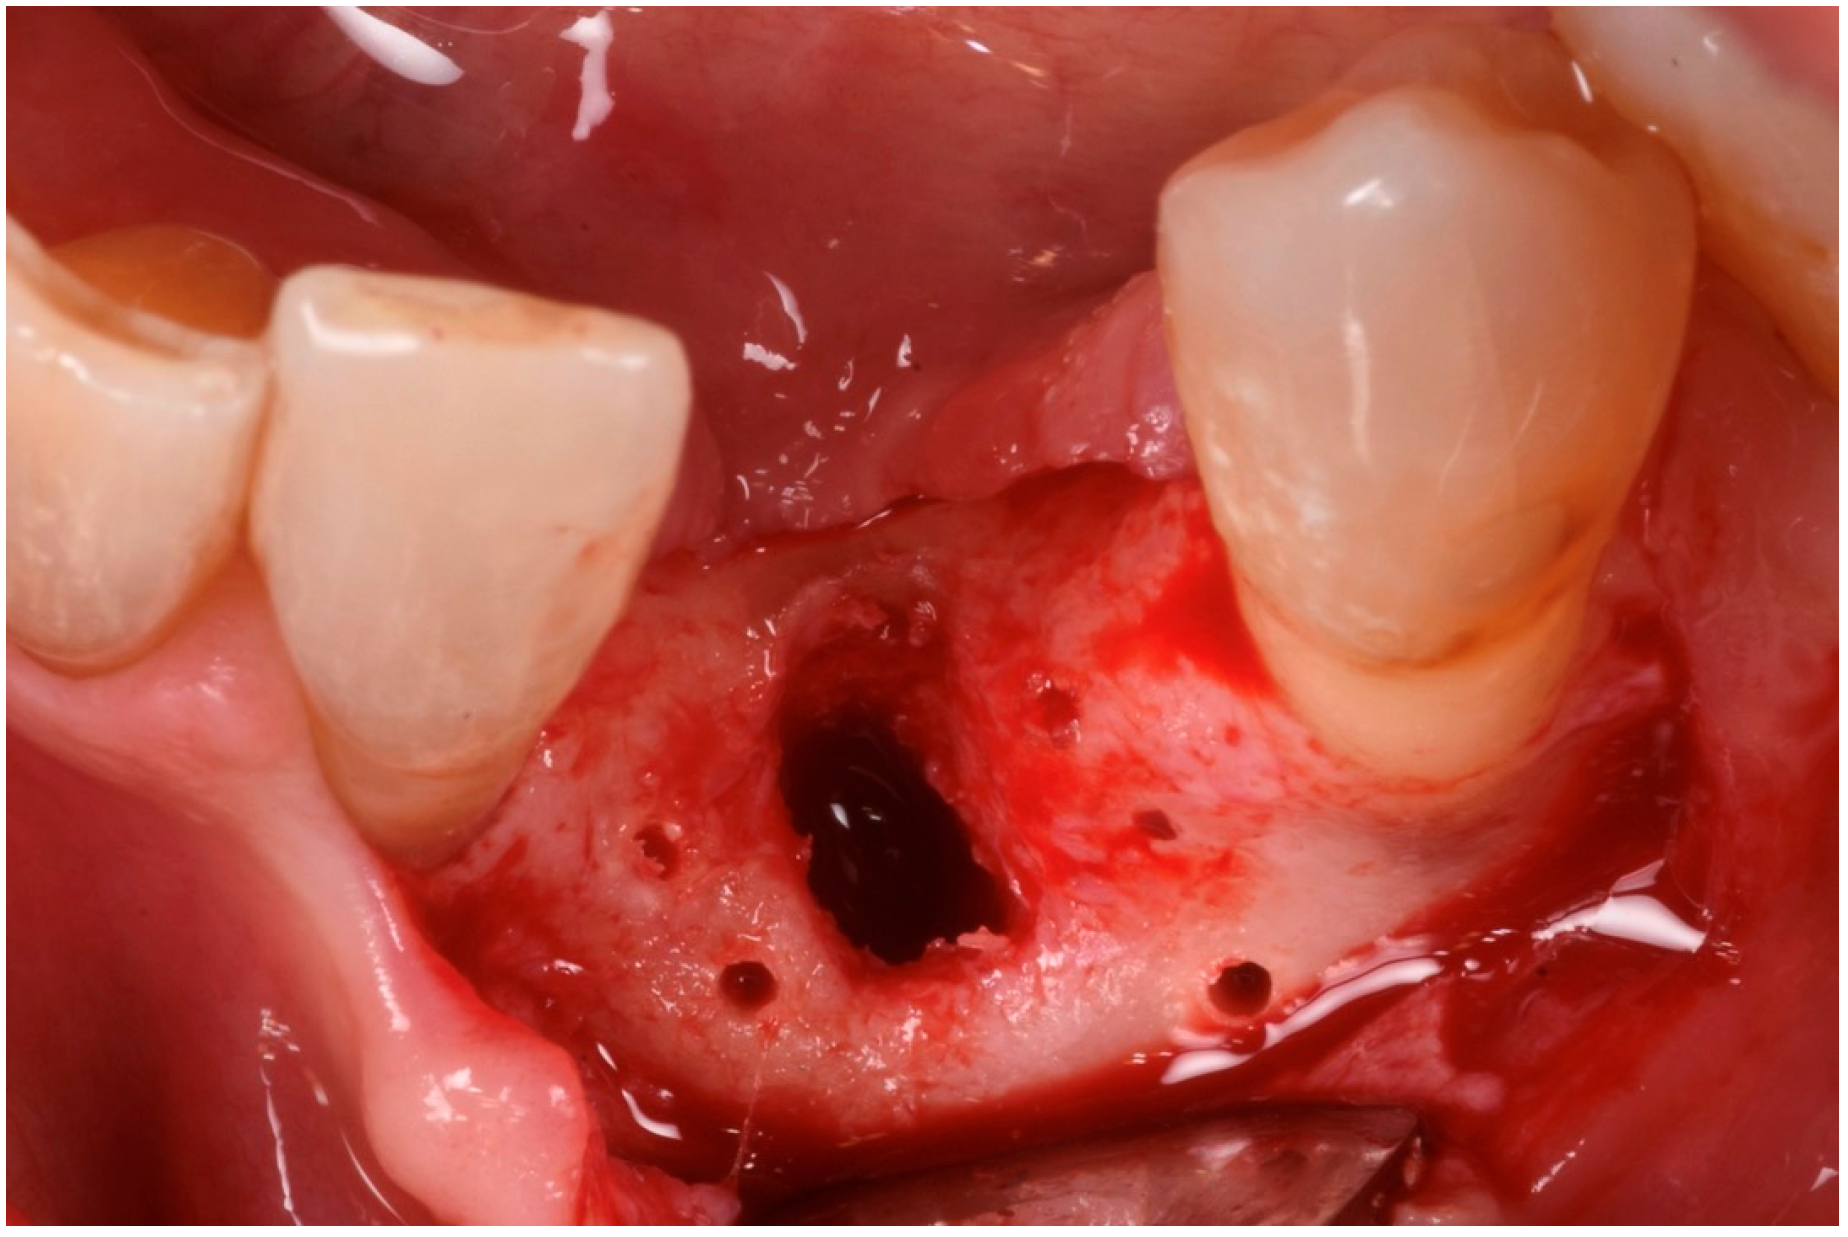

3.2. Hard Tissue Augmentation

The patient was anesthetized with articaine 1:200,000. A flap was designed to extend from the distal aspect of the lateral incisor to the distal of the first bicuspid. In this case, only one releasing incision was made distal to the bicuspid to provide greater flexibility at the mesial aspect, where bone loss was more advanced. A full-thickness buccal and lingual flap was elevated to expose the 3D lesion. The mesial–distal component of the defect measured 13 mm, with a significant portion of the buccal plate completely missing (Figure 4). The vertical component of the defect comprised 9 mm of suprabony component and 4 mm of infrabony component (Figure 5). The horizontal bone loss between the lingual and buccal walls was measured at 8 mm (Figure 6).

The blood clot was collected from the wound area and mixed with collagenated equine bone granules and autogenous bone scraped from the lingual side of the defect, along with a few drops of fibrin glue (FG) (Figure 7). This mixture ensured that the graft was both malleable and sticky, allowing it to adhere effectively to the base of the defect. The recipient site was prepared using a small round bur to create intramarrow penetrations, which facilitated additional bleeding and introduced mesenchymal cells from the marrow spaces (Figure 8). In this case, two different thicknesses of FCS were used: the thicker one (0.9 mm) was applied to restore the missing buccal plate, while a thinner FCS (0.5 mm) was utilized to protect the occlusal aspect of the defect and to seal the graft underneath (Figure 9 and Figure 10).

Figure 6. Occlusal view of the bone defect.

Medicina 61 00683 g006